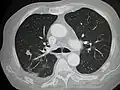

CT image of a lung metastasis -

Metastatic cancer in the lungs -